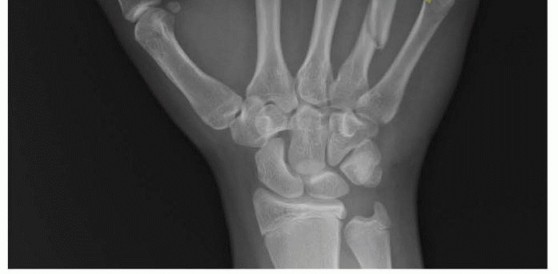

IMAGING AND OTHER DIAGNOSTIC STUDIES

The posteroanterior (PA) view can show shortening, especially relative to the adjacent metacarpals. Fracture angulation can be seen on the lateral view but is often best seen on the oblique view. Fractures of the base of the fifth metacarpal are best seen on the pronated oblique view.Specialized views of the metacarpal head can show the volar aspect (Brewerton) or the dorsal aspect (skyline).Traction views in the anesthetized patient may help elucidate pattern and extent of injury.Computed tomography (CT) scan can help in extensively comminuted fractures or articular injuries.